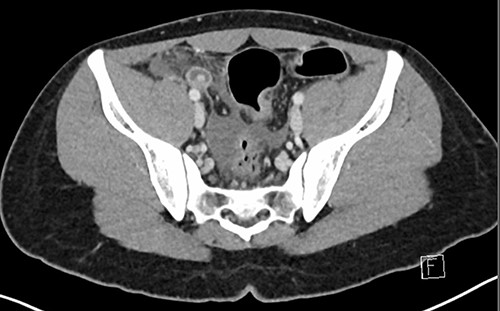

Investigations were arranged. His white cell count was 15.5 x 109/L and C reactive protein was 117 mg/L. An ultrasound of the abdomen showed a small volume of free fluid in the right iliac fossa but did not identify the appendix. A computed tomography (CT) scan of the abdomen was performed, which showed that the appendix was dilated to 13 mm with associated peri-appendiceal fat stranding and several hyperdensities measuring up to 8 mm within the base of the appendix (Figs 1 and 2).

Axial CT image demonstrating the inflamed appendix containing hyperdensities.